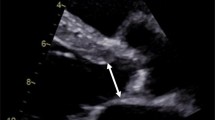

The main difference between TTE and TEE during the intraprocedural monitoring for TAVR is that TEE provides continuous monitoring during the procedure with higher image resolution but these advantages are at the expense of being more invasive (Table 3). Otherwise, both TTE and TEE offer comparable information to ensure appropriate THV placement and to identify periprocedural complication(s). In either modality, multiple views above, through, and below the THV with multiple-beat sweeps are essential to identify periprocedural complications, especially PVR (Fig. 3). As experience with TAVR has grown, there has been a further shift to using fluoroscopy alone to guide THV placement [29] and using TTE immediately after valve deployment to assure proper placement and to assess for valvular and perivalvular regurgitation.

a Mid-esohpageal LVOT long-axis view is revealing a posteriorly located PVR (white arrow). b midesophageal AV short-axis view demonstrated a posteriorly located PVR at 12 o’clock (white arrow). c Midesophageal AV short-axis view demonstrating a central, valvular, regurgitation secondary to incomplete expansion of the prosthetic valve (red arrow). d Transthoracic PLAX view showing an anteriorly located PVR (yellow arrow). e Transthoracic PSAX view showing an anteriorly located PRV at 1 o’clock (yellow arrow). f Transthoracic A3C view showing a regurgitation jet that is difficult to determine its mechanism, PVR versus valvular regurgitation, from the same patient in panel D and E (yellow arrow). A3C apical 3-chamber, Ao aorta, LA left atrium, LV left ventricle, LVOT left ventricular outflow tract, PLAX parasternal long-axis, PSAX parasternal short-axis, PVR paravalvular regurgitation, RA right atrium, RV right ventricle